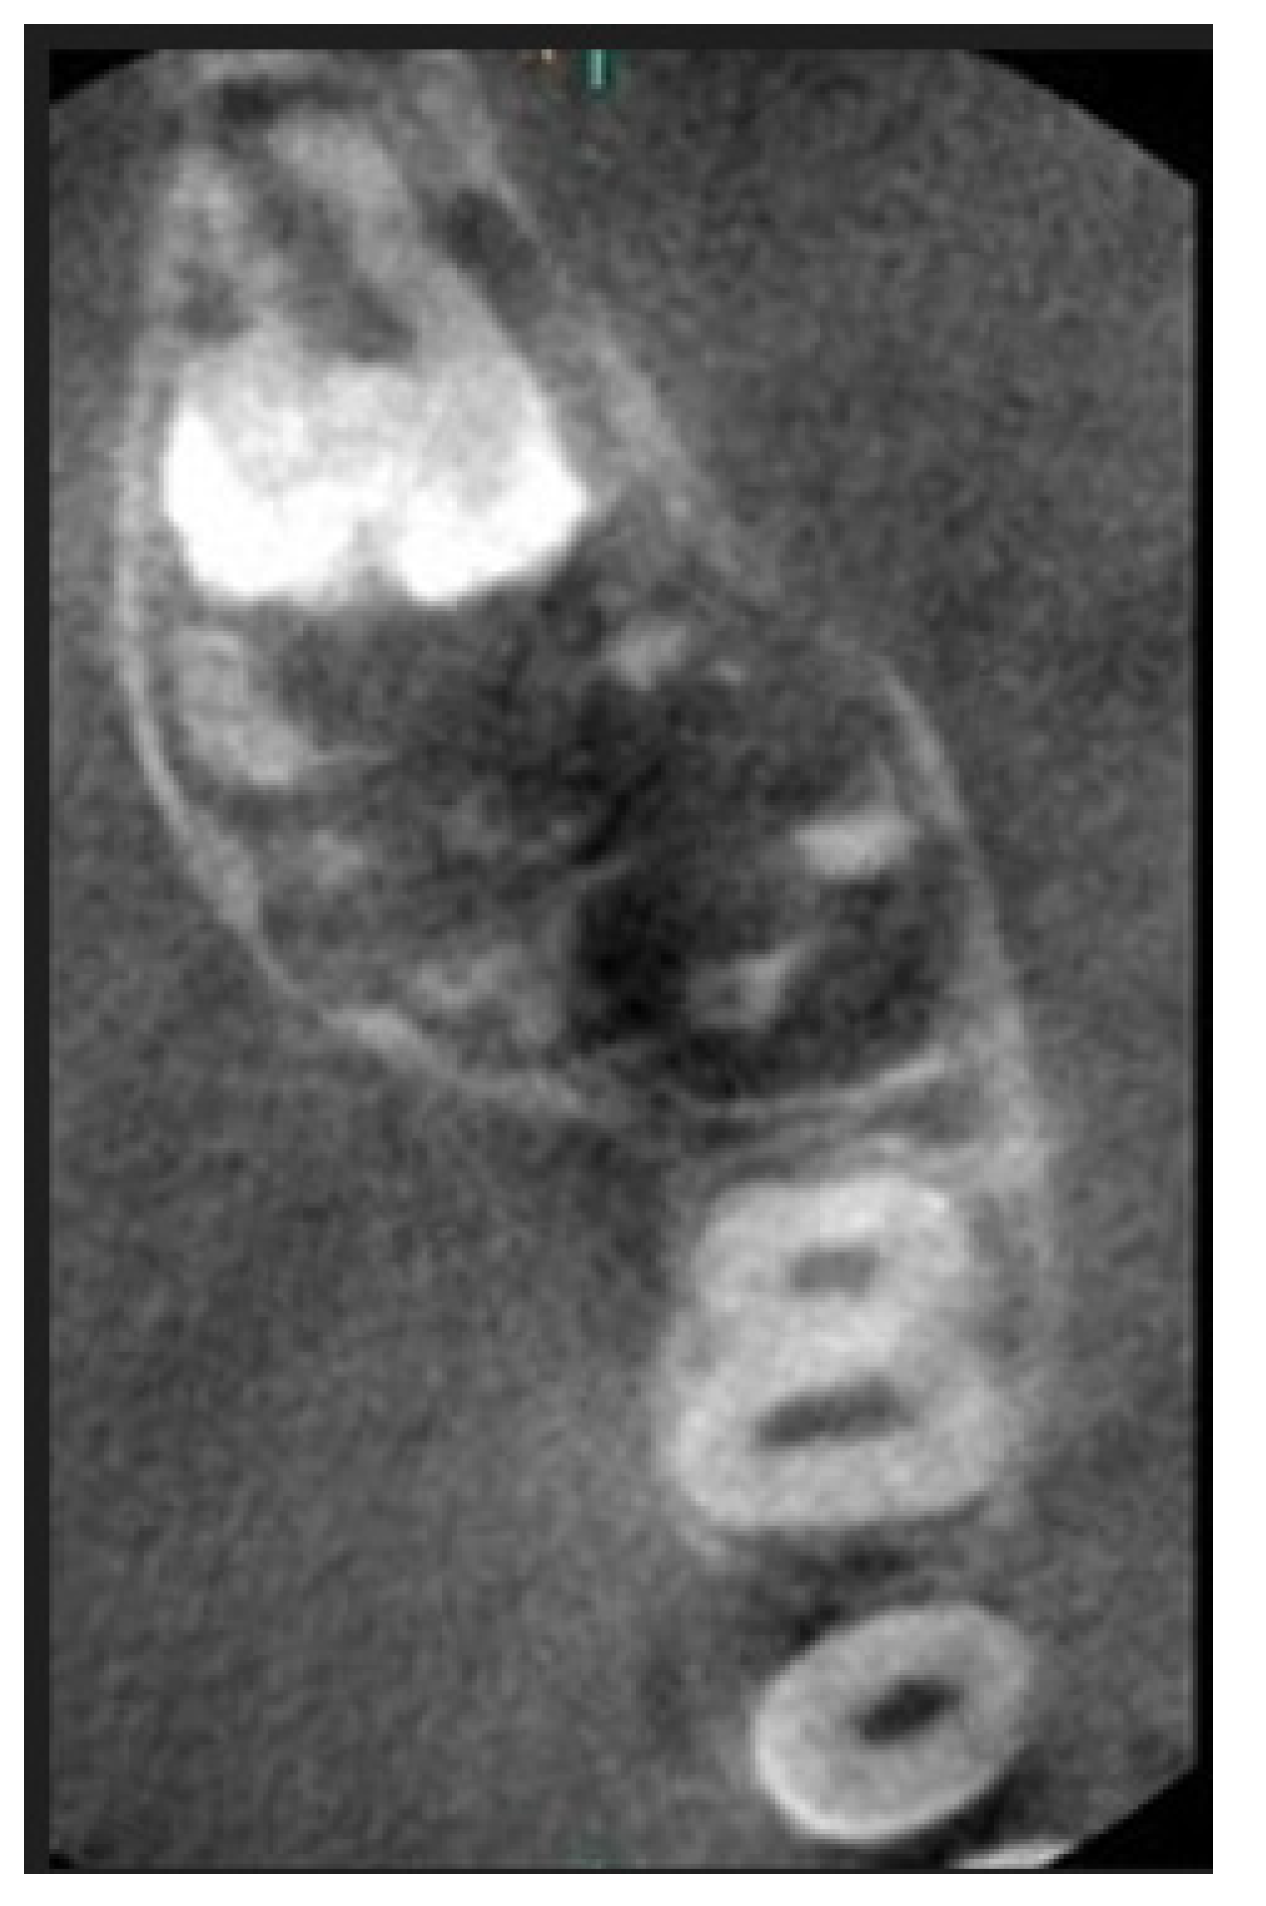

2. Case Report Presentation